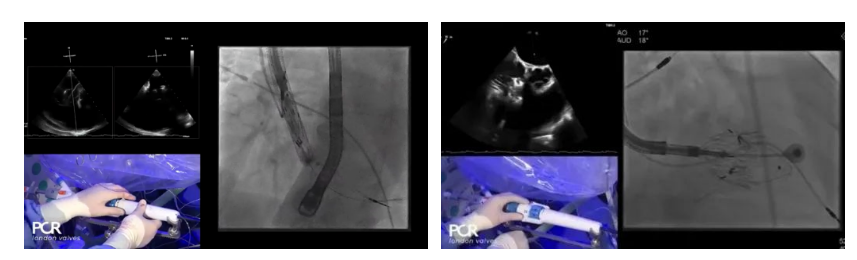

Thomas Modine教授的線上指導下,德國Mainz中心Ralph Stephan von Bardeleben教授完成了LuX-Valve Plus經血管三尖瓣置換系統(tǒng)在其所在中心的首例植入,術后Stephan教授高度贊揚LuX-Valve Plus人工三尖瓣瓣膜“植入過程高度可控,安全有效”。接受治療的是一例82歲的高齡男性患者,術前NYHAⅢ級,因復發(fā)心衰入院,有逾5年的慢性房顫病史。這例患者因特殊的解剖結構以及較大的三尖瓣瓣環(huán),有起搏器植入史,被所有其他經導管三尖瓣修復或置換器械的臨床排除在外,因此等了一年半才等到此次LuX-Valve Plus的手術機會,實屬不易。

手術在全麻狀態(tài)下開展,采用經右側頸靜脈入路的方式將輸送器送入患者心臟內,在TEE及DSA引導下調整輸送器頭端角度,使得輸送器與三尖瓣瓣環(huán)平面垂直。在輸送器進入右心室后釋放室間隔錨定裝置,而后釋放瓣葉夾持件(2個耳片結構)成垂直狀態(tài)。在TEE及DSA確定夾持件固定至三尖瓣葉根部且位于右室側后釋放人工瓣心房側盤片。隨后調整瓣膜同軸性以及室間隔錨定件位置(貼合室間隔),前推藏針管并固定,進而釋放室間隔錨定裝置,并再次確認瓣膜位置、穩(wěn)定性及同軸性,合攏輸送鞘后撤出輸送器,完成LuX-Valve Plus人工三尖瓣瓣膜的植入。